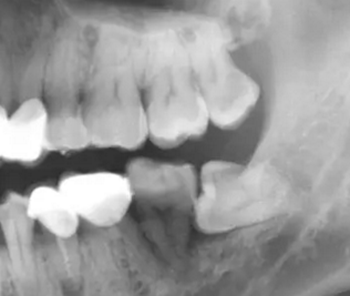

防治:牙拔除術(shù)后應(yīng)仔細(xì)清理牙槽窩,特別是慢性根尖周炎的患牙,根尖炎性病灶不刮治干凈,即可發(fā)生拔牙術(shù)后出血,也可形成慢性炎癥而長期不愈。多根牙拔除時(shí)應(yīng)防止殘根遺留。如發(fā)生慢性感染,應(yīng)拍攝X線片,了解牙槽窩內(nèi)病變情況,是否有異物遺留,牙槽窩的愈合情況等,然后在局麻下,重新進(jìn)行牙槽窩的刮治,讓血液充滿后,消毒紗布棉卷壓迫止血,并給予口服抗生素治療。